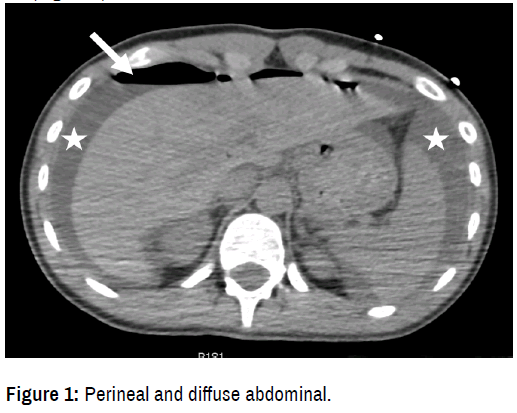

On September 2016, a 19-year-old patient with only past medical history of humeral fracture was sitting as a rear PWC passenger and fell off of the back of the watercraft. Wearing a standard 2-piece swimsuit and a life jacket, she experienced severe perineal and diffuse abdominal pain with vomiting. The victim was quickly taken to the Emergency Room where she remained haemodynamically stable. The clinical examination found a 5-centimeter wound of the anus with sphincter injury and rigidity of the external abdomen. An abdominal computed-tomography scan confirmed major intraperitoneal effusion and free air associated with intraperitoneal faeces in pelvic region and two spleen parenchymal lacerations AAST grade 3. Diagnosis of rectal or rectosigmoid perforation was strongly mentioned. The rectoscopy notice posterior lacerations of the internal and external anal sphincter, superficial rectal lacerations and complex perforation of the rectosigmoid junction [2]. Exploratory laparoscopies then a conversion to laparotomy were urgently performed. The 4L haematic effusion with multiple water debris and the localized fecal peritonitis were treated by peritoneal lavage. No laceration was noticed on the spleen. The patient underwent a Hartmann’s procedure with loop colostomy, drainage and transanal sphincter repair. Antibiotics by Amoxicillin and clavulanic acid were then administrated and a wound infection treated by opening and incision packing. The patient was discharged on postoperative day 12. Five months later, colostomy takedown and reanastomosis were performed without difficulty. Normal bowel function has returned so far without any continence issue (Figure 1).

Figure 1. Perineal and diffuse abdominal.